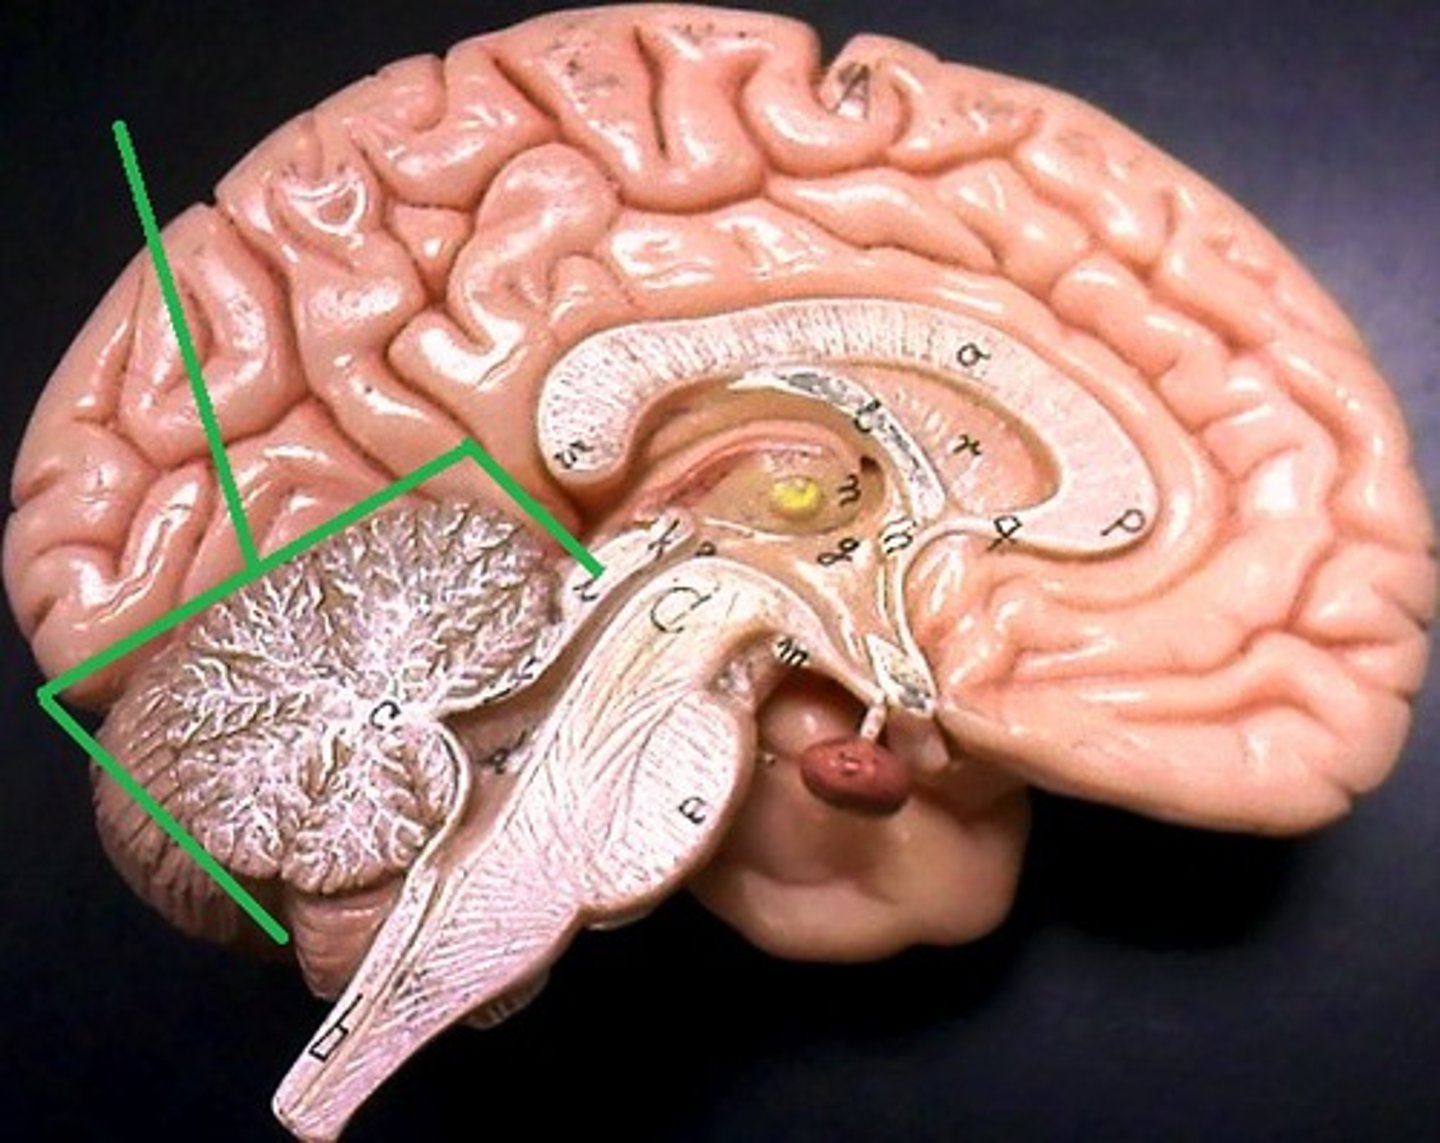

corpus callosum

septum pellucidum

fornix

diencephalon

pineal body (pineal gland)

thalamus

hypothalamus

infundibulum

pituitary gland

mammillary bodies

midbrain (mesencephalon)

pons

medulla oblongata

cerebellum

right and left lateral ventricles

third ventricle

fourth ventricle

cerebral aqueduct (mesencephalic aqueduct)

interventricular foramen